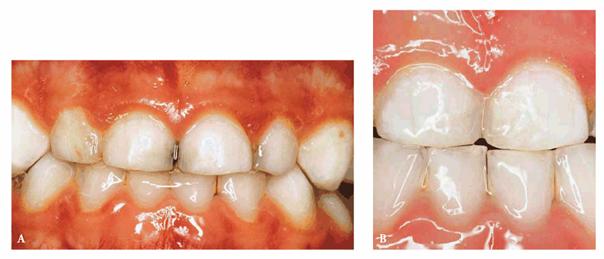

A male patient, 2 years and 8 months old, with interproximal caries of D, E, F,

and G (Figures 27-1A

and B

Figure 27-1A and B: Interproximal caries of frontal anterior teeth are removed, and a morphic-functional composite restoration is performed.

PROBLEM: The patient was not compliant, but an initial radiographic

examination was accomplished.

TREATMENT: Under conscious sedation, in only one visit, caries lesions

are removed, and the morphic-functional restoration with composite resin is

placed.

RESULT: The restoration achieved the esthetic goal and restored function

and anatomy. Furthermore, in a situation of tooth crowding, the arch length was

preserved. Both the patient and his parents were pleased.